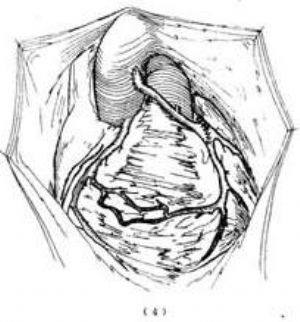

(2)用大隱靜脈行主動脈-左冠狀動脈傍路移植術:1966年Cooley,1973年El Said,1974年Neches,1980年Arciniegas等先後應用一段倒轉的自體或同種大隱靜脈、鎖骨下動脈或絛綸人造血管聯接於升主動脈與左冠狀動脈切端之間。供作移植術的血管一端與升主動脈作端側吻合術,另一端與左冠狀動脈作端側或對端吻合術。採用端側吻合術者則在靠近肺動脈壁處遊離左冠狀動脈起始部,用縫線雙重結紮,再縱向切開左冠狀動脈總幹,大隱靜脈越過肺動脈總幹前方與左冠狀動脈行端側吻合術(圖2)。採用對端吻合術者,則從肺動脈將左冠狀動脈開口連同其四周的肺動脈壁切下,縫合肺動脈壁切口。再遊離近段左冠狀動脈與大隱靜脈作對端吻合術。對端吻合術的操作技術較之端側吻合術難度較小。施行端側吻合術可以不用體外循環。由於嬰幼兒病例的冠狀動脈和大隱靜脈均較細小,且血管壁薄弱,術後較易發生梗阻性病變或血管腔擴大等併發症,長期通暢率及治療效果尚有待隨訪觀察。

圖2 主動脈-左冠狀動脈、大隱靜脈旁路移植術

⑴左冠狀動脈起源於肺動脈,冠循環逆流入肺動脈;⑵結紮左冠狀動脈起始部;⑶用大隱靜脈作主動脈-左冠狀動脈旁路移植術;⑷完成移植術